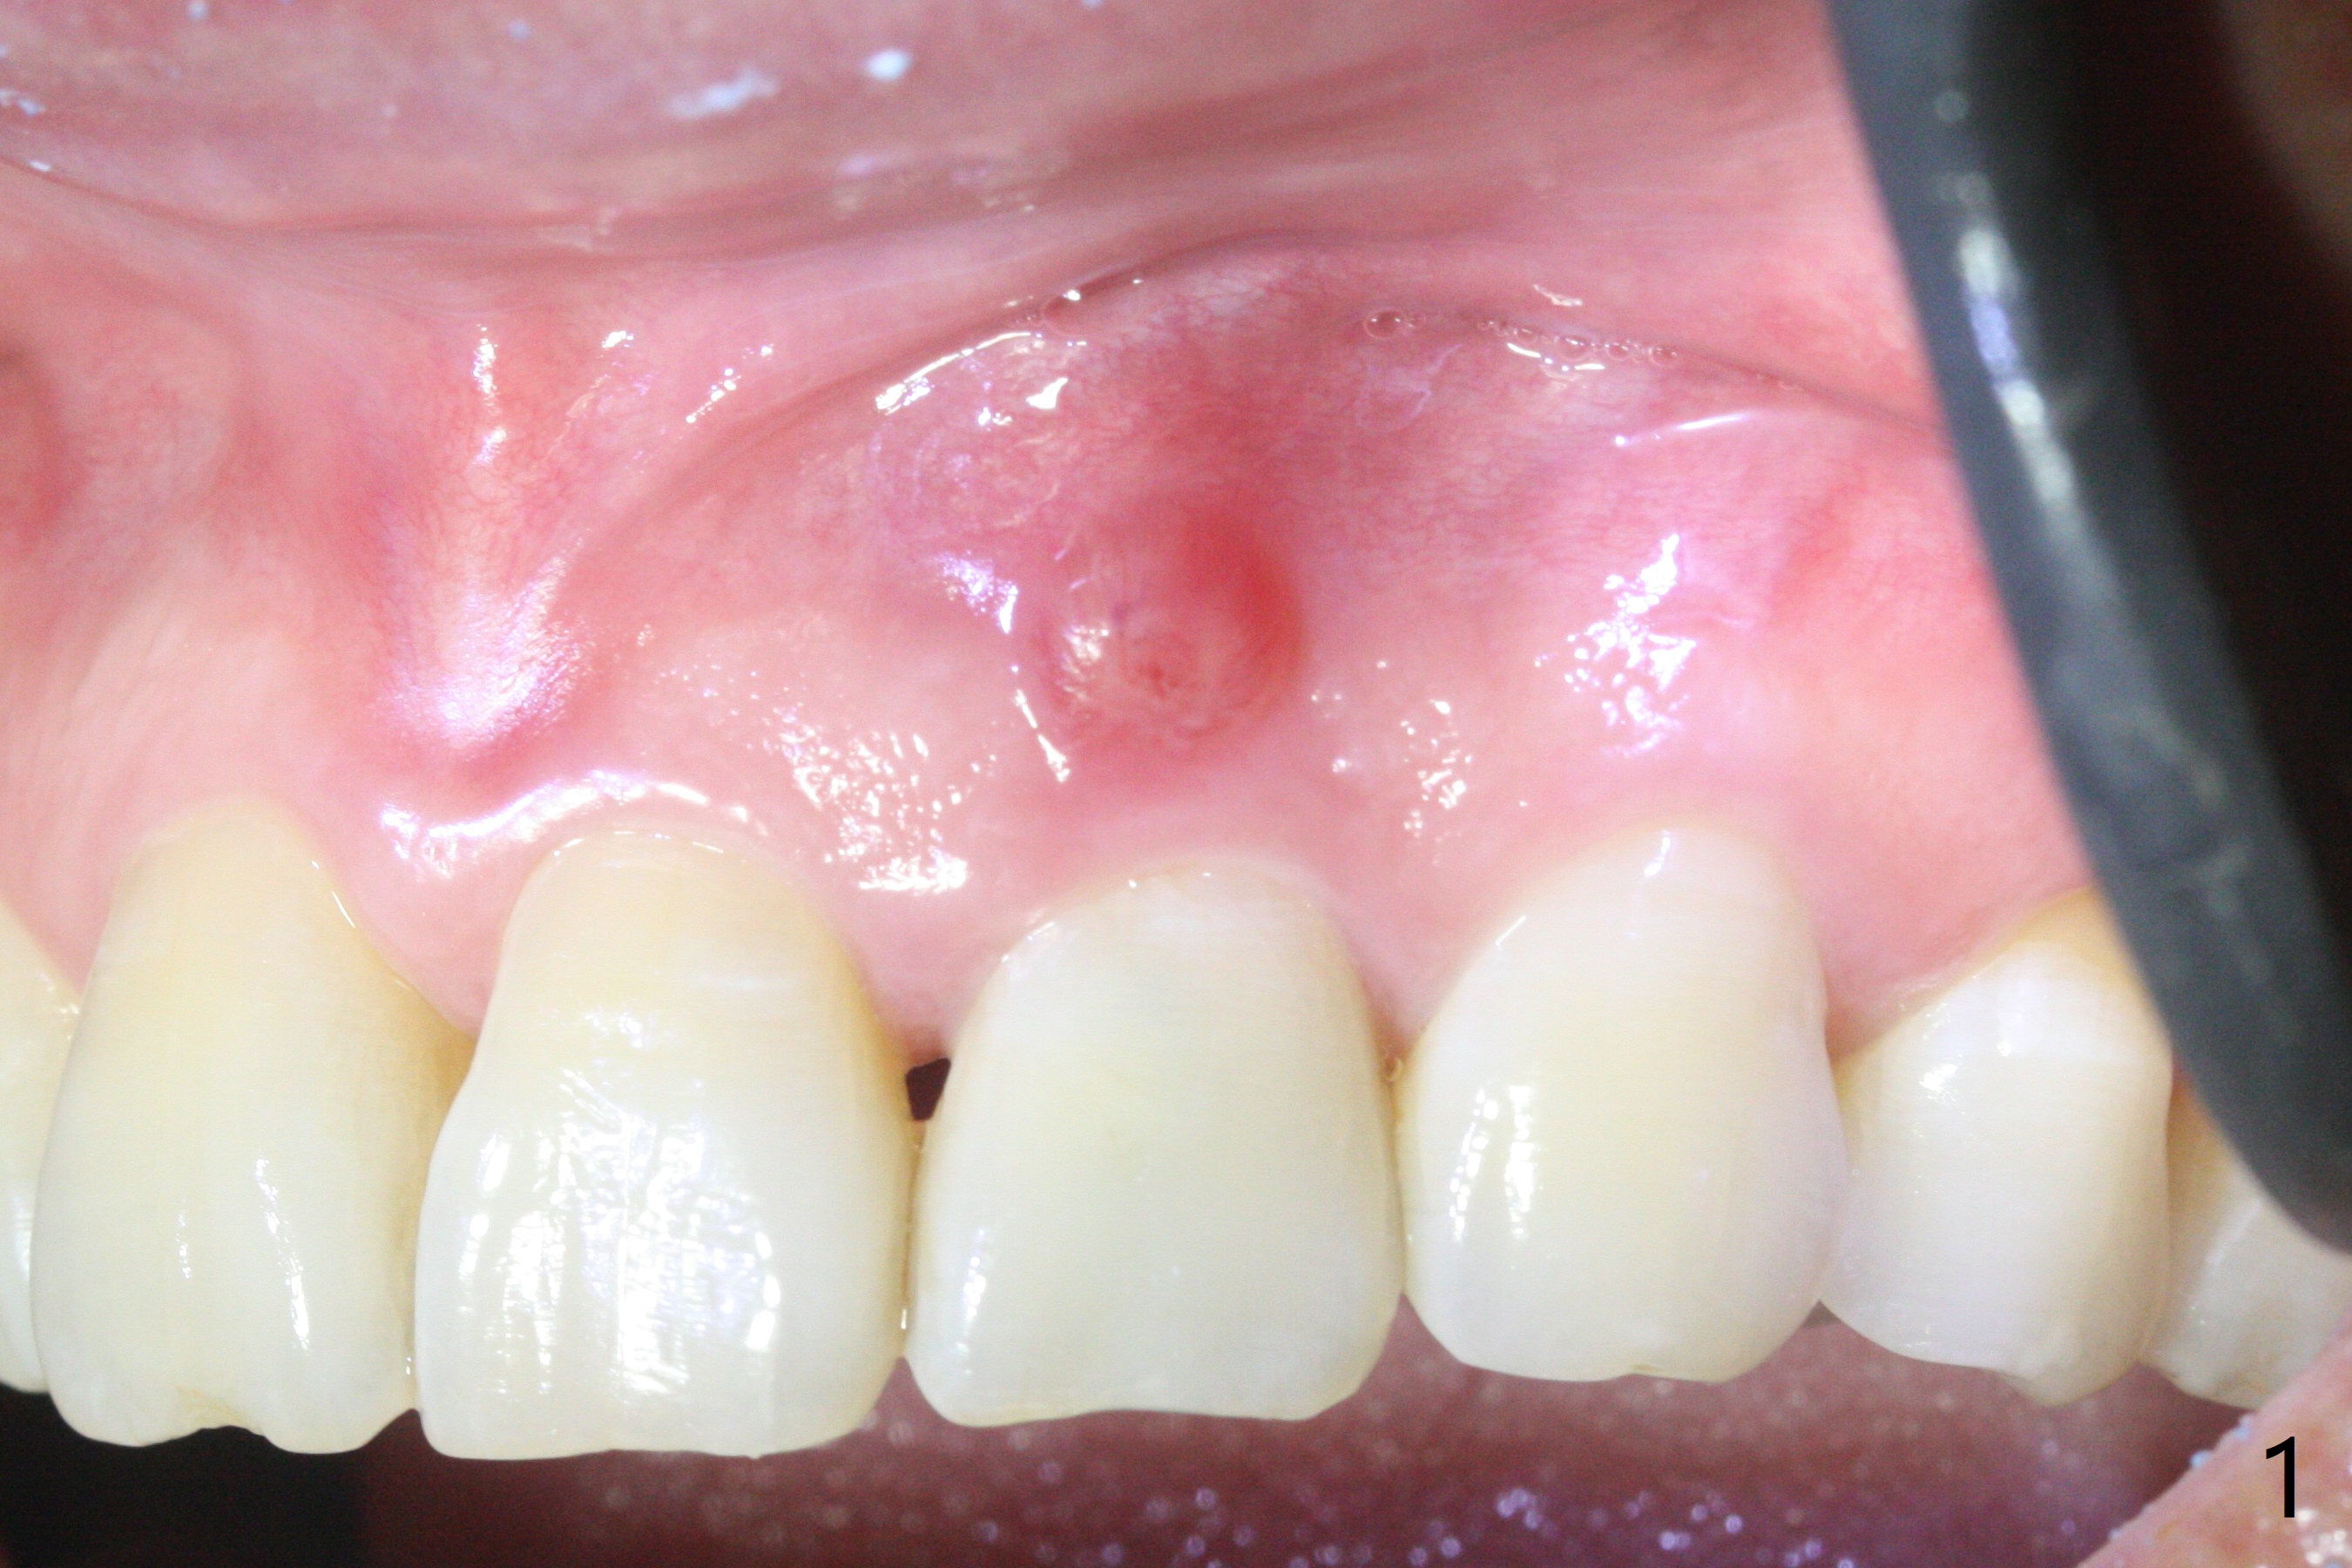

病人回来带来瘘道(图一),不过不会增加难度,病牙去除,它便自动消失。尽管颊侧骨壁完全失去,颊侧牙龈仍丰满(图二),为什么呢?第一,因为粗大牙根存在,第二两旁牙齿,牙槽骨撑着帐篷(侧切牙颊侧牙龈),第三,牙冠。为了防止术后牙龈塌陷,尽量不切开,即刻放置植体(牙根);由于前牙缘故,这次植体不能很大,所以植骨必须过度(over grafting),最后即刻制作临时牙冠,撑住牙龈。这就是所谓每个人进入角色。这个牙根有一种先天性畸形:dens in dent (图三(腭侧观):箭头)。尽管腭侧牙根畸形,腭侧骨壁吸收临床上并不严重,所以钻洞仍偏腭侧。当预定最后钻头还在钻洞时,填入大量粘性骨块(图四:*),细长植体还没有完全卡入鼻底(图五),最后好像可以(图六,七)。植体,骨粉入位(图八),最后临时牙冠出场(图九)。尽管植体小,术后一周临时牙冠仍然可以维持牙龈原有形状(emergency profile,图十:箭头(*:树脂强化牙冠固定))。图十一以不同角度显示瘘道缩小。术后三周取出有些松动的临时牙冠,骨粉虽然还没有被肉芽组织整合,但是显得正常,周围牙龈健康(图十二)。术后4个月牙龈形态正常(图十三),没有触痛;颊侧骨板轻度凹陷(图十四);骨粉仍在原位(图十五)。术后7个月骨粉仍在原位(图十五,十六,但是冠部密度减低(可能骨粉流失,需要牙周或者树脂敷料保护)),没有螺纹暴露。但是牙冠边缘暴露,说明牙龈收缩(图十七,与图十三对比),颊侧骨板仍塌陷(图十八)。插入龈线取得多个目的:修整基台边缘,取模,颊侧牙龈推向颊侧,有利于即将衬里牙冠龈缘进入龈下(图十九)。取模后牙冠边缘(图二十:<)衬里,然后修整,变窄,以便插入龈下,促进颊侧牙龈下降(图二十一,二十二)。术后8个月牙冠粘固前牙龈健康(图二十七,八),牙冠(图二十九)固位后,病人满意(图三十),咬合调整(图三十一),注意腭侧粘固粉流出通道(<)。